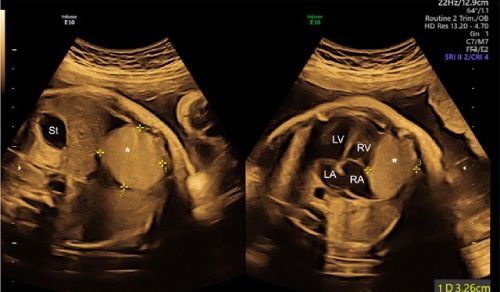

At the Children's Hospital of New York, our pediatric cardiologists, interventional cardiologists, and cardiovascular surgeons from Columbia and Weill Cornell Medicine collaborate seamlessly to manage every form of heart disease in infants and children. Our teams work tirelessly to provide treatments for the most complex heart diseases with the latest imaging technologies, medical therapies, and surgical, transcatheter and hybrid procedures.

Pediatric Cardiology (Heart)